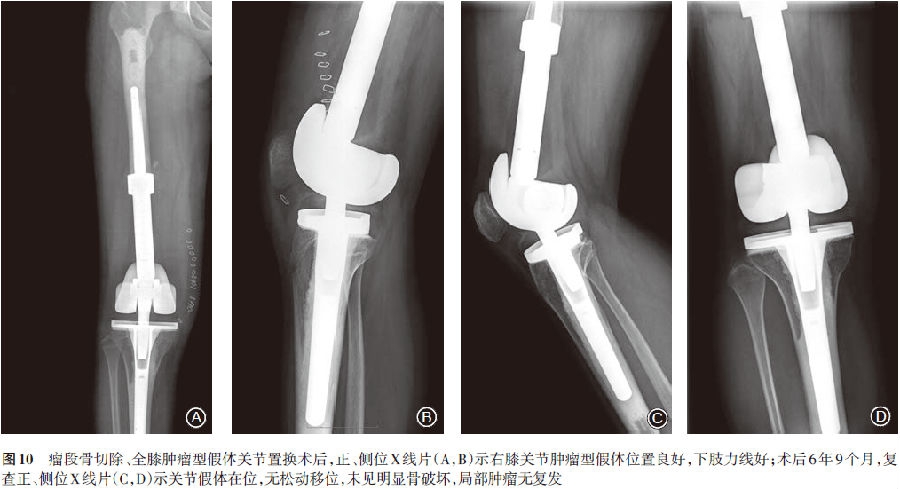

术后再次予以相同方案化疗2个疗程,复查肺部CT未见明显异常,正、侧位X线片示右膝肿瘤假体位置良好(图10A,B)。目前患者保肢手术后7年余,定期随访复查未发现局部复发(图10C,D)及远处转移证据,临床治愈。